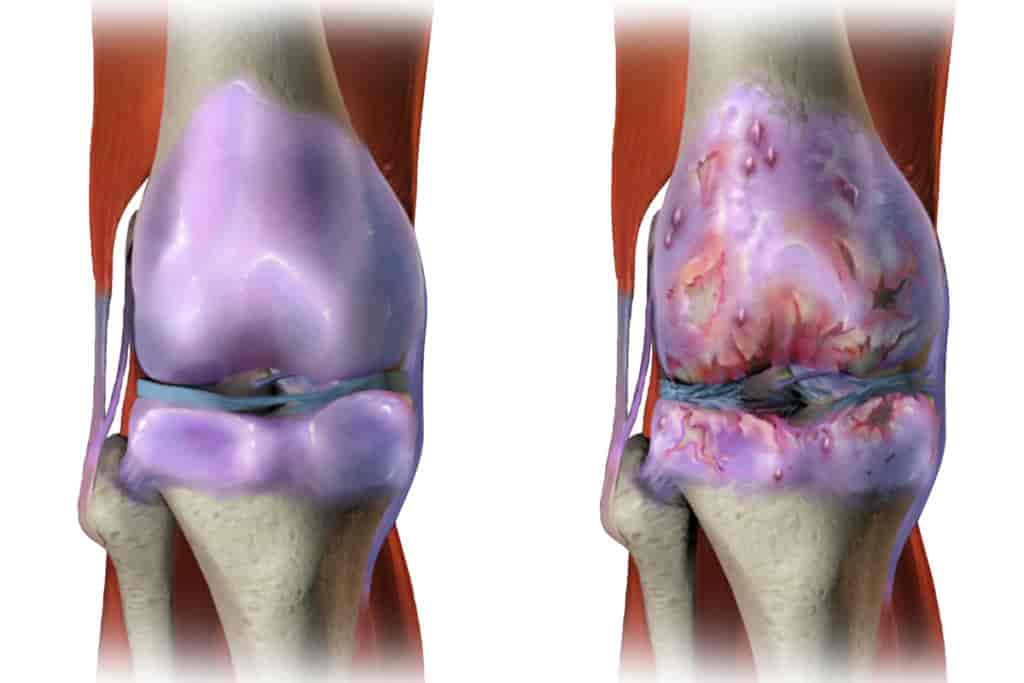

(Ang malusog na joint (kaliwa) at ang joint na apektado ng arthrosis. Sa kawalan ng supportive therapy, tuluyang "kinakain" ng arthrosis ang cartilage tissue.)

(Ang malusog na joint (kaliwa) at ang joint na apektado ng arthrosis. Sa kawalan ng supportive therapy, tuluyang "kinakain" ng arthrosis ang cartilage tissue.)